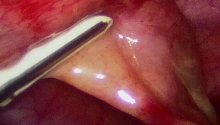

• 2. 使用环状接头

1.jpg

有些制造商提供一个消毒的环状接头,可以放置在摄影机和内视镜之间。理论上,这些环状接头非常实用,因为它们可以使医师改变接到摄影机上的内视镜。实际上,从内视镜移开镜头2 cm 会缩小视野,减少亮度和损失影像质量。